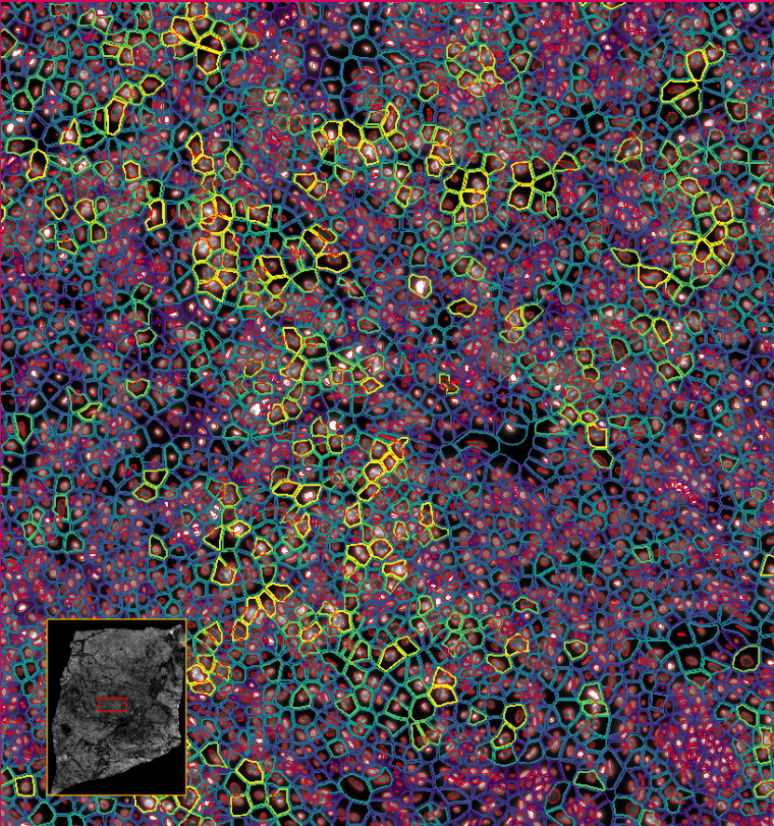

image.png

ͼ2£ºXeniumÊý¾Ý¸ÅÀÀ